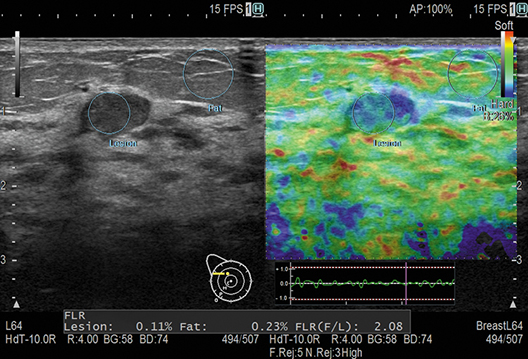

La selección automática de encuadre (AFS) selecciona el encuadre adecuado para la medición en la elastografía de tejidos en tiempo real. La relación de tensión asistida (Assist Strain Ratio, ASR) localiza automáticamente la región de interés (Region of Interest, ROI) de la medición. Ahora se pueden completar pasos de medición complejos y repetitivos con un solo botón.